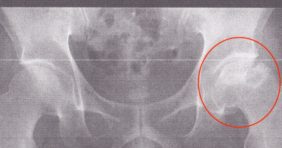

日本全国で120人以上に 店舗せどりのコンサルをしてきましたが、 突発性大腿骨頭壊死症のフジップリンです! 〜今日のあらすじ〜 俳優さんでも話題になっていますね。 突発性大腿骨頭壊死症(股関節骨頭壊死症)という難病の話し … 続きを読む 日本一明るい、突発性大腿骨頭壊死症(股関節骨頭壊死症)のフジップリンです!